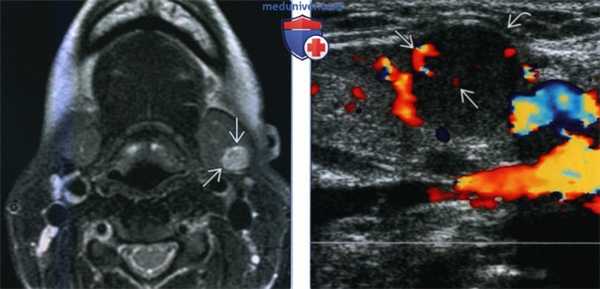

(Слева) МРТ Т2ВИ, аксиальная проекция, молодая пациентка с пальпируемым образованием в поднижнечелюстной области. В левой поднижнечелюстной железе видно гиперинтенсивное образование овальной формы. Признаков распространения за пределы железы нет.

(Справа) Допплеровское УЗИ, продольная косая проекция, эта же пациентка. Солидное образование с четкими контурами в левой поднижнечелюстной железе. Контуры железы деформированы. Кальцификатов или кист в толще железы нет. На периферии и в центре опухоли кровоток сохранен.